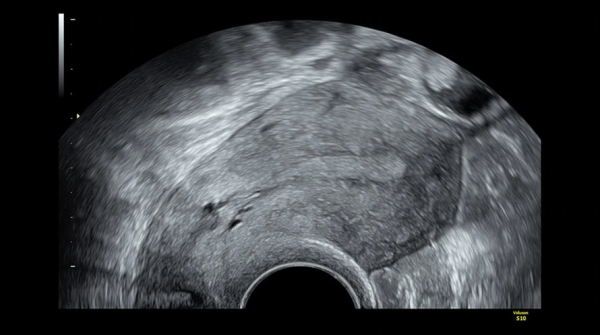

- Репродуктивной медицине для визуализации фолликулов, маточных труб и переноса эмбриона;

- Гинекологии для исследований аномалий матки, мышц тазового дна.

- Детализированное и четкое изображение в 2D режиме.

- Исключительную глубину проникновения с неизменным качеством изображения для возможности принять даже самых трудных для визуализации пациентов.